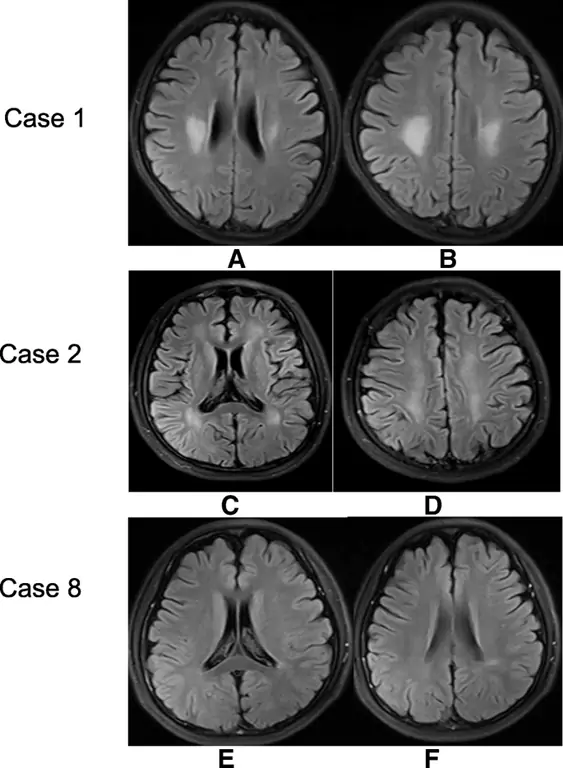

При обнаружении нейровизуализации преобладали церебральная атрофия различной степени (11/16), за которой следовали высокоинтенсивные поражения белого вещества (4/16), поражения мозжечка (1/16), атрофия мозжечка (1/16) и поражения спинного мозга. (1/16). Были также 2 пациента с нормальной визуализацией (Таблица 2). В отличие от диффузного набухания белого вещества в ранних случаях cblC, поражения белого вещества в этих поздних случаях представлены двусторонними симметричными пятнистыми повреждениями, главным образом в центральном яичнике, лучистой короне и перивентрикулярной области (Fig. 1a-d). Случай 8 представил только небольшие поражения в односторонней задней желудочковой области (Fig. 1e, f). Поражения мозжечка редко сообщалось в случаях cblC. В этом исследовании двусторонние поражения коры мозжечка были обнаружены в одном случае (впервые сообщалось в нашем предыдущем докладе (8)) и атрофия мозжечка в случае 13 (Fig. 2a, b). МРТ спинного мозга показала повреждения спинного мозга в случае 1 (рис. 2в, г), и после лечения повреждения исчезли. Ни в одном из случаев не было выявлено поражений базальных ганглиев, гидроцефалии или разбухания диффузного белого вещества, которые были общими признаками при раннем начале заболевания кобаламином С. Только в случае № 4 имелись данные МР-спектроскопии из областей двустороннего поражения центрального яичника и короны, которые показали снижение пика N-ацетиласпартата (NAA) и увеличение пика холина (Cho) и лактата (Lac) в очагах поражения с обеих сторон.

фигура 1

Повреждения белого вещества в трех случаях с поздним началом заболевания ХБС. МРТ головного мозга в случае 1 в таблице 1 показала симметричные пятнистые поражения в лучистой короне (а) и в центральном овале (б). МРТ головного мозга в случае 2 в Таблице 1 показала симметричные пятнистые поражения в двустороннем перивентрикулярном белом веществе, особенно в задней области (с) и коронарной радиации (d). МРТ случая 8 в таблице 1 показала небольшие поражения в односторонней задней желудочковой области (е, е). Повреждения белого вещества в этих трех случаях представляли гиперинтенсивность на изображении с восстановлением инверсии (FLAIR) с ослабленной жидкостью

Изображение в полном размере